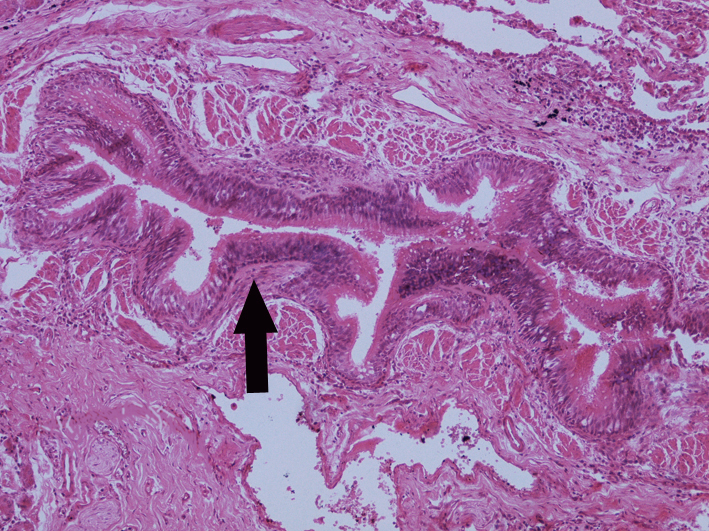

4.支气管扩张症